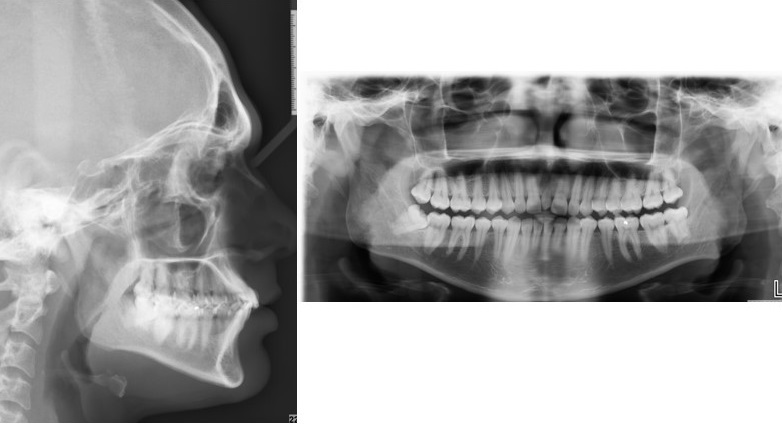

In our study, 15.24% had the presence of at least one DA. Our study included the entire spectrum of DA (Figs. 3-5). The results of our study demonstrated an increased frequency of type II and III STB (complete calcification) in patients with DA, which was statistically significant when compared to the control group. Previous studies reported the incidence of STB that ranged from 9.67 to 25.8 in patients with buccal and palatal impacted canines [11-13], 6 to 21.7% in patients with hyperdontia, 23.8% in patients with dental transposition [14], 15 and 18.7% in patients with agenesis [2], 13.3% in patients with highly placed canines [15] and 14.3% and 16.7% in patients with palatally displaced canines [2, 9].